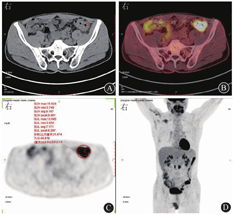

2021年4月13日完善18F-氟代脱氧葡萄糖(18F-fluorodeoxyglucose,18F-FDG)正电子发射计算机体层显像(positron emission tomography and computed tomography,PET/CT)检查示结肠多发节段性18F-FDG代谢增高灶(图1),最大标准摄取值(maximal standardized uptake value,SUVmax)为15.6(降结肠-乙状结肠移行部);肠旁可见多发小淋巴结影,部分18F-FDG摄取略增高;纵隔4R区(右下支气管旁淋巴结)见一增大淋巴结影,大小约为0.9 cm×0.6 cm,18F-FDG摄取增高(SUVmax为2.2),考虑炎症改变;鼻中隔右偏、双下鼻甲肥大;双侧上颌窦炎症;所示诸骨结构完整,未见异常18F-FDG浓聚或缺损灶;其余脏器未见异常18F-FDG摄取。

2021年5月25日患者转入厦门大学附属中山医院血液内科进一步诊治,复查EB病毒DNA为1.03×105拷贝/mL。完善纤维鼻咽镜与喉镜检查,可见鼻咽部光滑,会厌光滑;双侧声带光滑,活动可。双侧颈部、腋窝、腹股沟超声检查示多个增大淋巴结,其中颈部最大者约2.3 cm×0.7 cm,腋窝最大者约1.7 cm×0.7 cm,腹股沟最大者约2.1 cm×0.5 cm,边缘光整,形态规则,部分淋巴门未见,可见血流信号。建议完善淋巴结穿刺活检,患者拒绝。完善骨髓穿刺检查,骨髓象未见明显异常,可见散在少量淋巴细胞,未见异型细胞;EBER阴性。综合上述临床资料,最终诊断为非上呼吸道消化道自然杀伤/T细胞淋巴瘤(non-upper aerodigestive tract NK/T-cell lymphoma,NUAT-NKTCL)(Ⅳ期),高危。予P-GEMOX方案(培门冬酶+吉西他滨+奥沙利铂)规律化学治疗。2021年8月25日复查结肠镜示乙状结肠距肛门20 cm处可见手术瘢痕,黏膜光滑;全结肠、直肠未见明显溃疡、糜烂(图6)。次日复查盆腹腔增强计算机体层成像示乙状结肠术后改变,吻合口壁稍增厚,较前缓解,周围未见明显渗出液(图7)。复查超声示双侧颈部、腋窝、腹股沟可见多个肿大淋巴结,颈部淋巴结最大者约1.4 cm×0.4 cm,腋窝淋巴结最大者约1.5 cm×0.5 cm,腹股沟淋巴结最大者约0.8 cm×0.3 cm,边缘光整,形态规则,部分淋巴门未见,可见血流信号。至截稿,患者接受规律随访,病情平稳。

血液内科张可杰主任医师:结外自然杀伤/T细胞淋巴瘤仅累及消化道者很少见,需注意排查是否存在鼻咽部受累、骨髓受累等情况。进一步完善纤维鼻咽镜与喉镜检查未见异常。骨髓穿刺活检未见异常。超声检查见多发淋巴结肿大,因其形态规整,且此前PET/CT检查未见高代谢的淋巴结病变,考虑为非特异性淋巴结炎可能性大。建议患者行淋巴结穿刺活检以明确病变性质,并评估是否可作为治疗效果的评价指标,患者表示拒绝。患者结肠播散性受累,瘤体侵破浆膜层,根据Lugano分期标准[14,15],诊断为NUAT-NKTCL(Ⅳ期),高危。NUAT-NKTCL 5年生存率为9%~22%[15]。Ⅰ~Ⅱ期自然杀伤/T细胞淋巴瘤应采用同时或序贯化学治疗、放射治疗的方案,Ⅲ~Ⅳ期患者应以含培门冬酶的联合化学治疗为主[16,17]。免疫检查点抑制剂可用于复发/难治性病例的治疗,部分晚期患者可考虑采用造血干细胞移植[4,17]。向患者解释病情和治疗方案,经其同意,排除禁忌证后采用P-GEMOX方案(含培门冬酶、吉西他滨和奥沙利铂)化学治疗。患者规律化学治疗3个月后复查肠镜提示溃疡消失,复查计算机体层成像仅见吻合口稍增厚,无腹水,嘱其继续在血液内科随诊治疗观察。